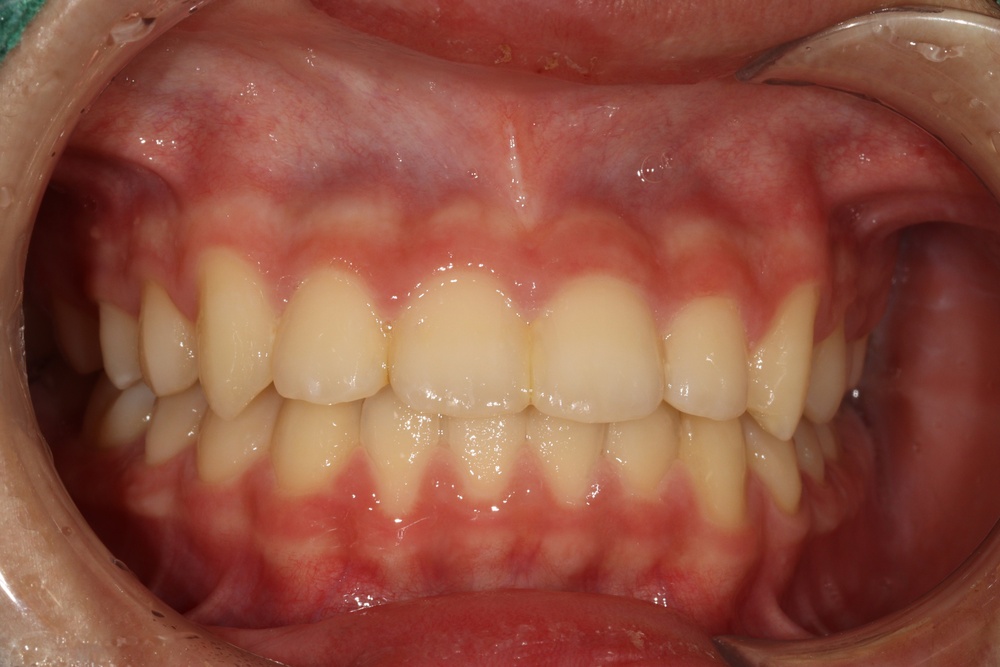

이전에 다쳐서 타치과에서 레진으로 때운 앞니가 시리다고 하셔서 신경치료를 먼저 진행했습니다.

뻗친 앞니를 넣기 위해 위쪽만 작은어금니를 2개 발치하고 공간을 닫았습니다.

교정치료 마무리 단계에서 보철(크라운)을 제작하여 앞니에 끼워드렸습니다.

치료 후 위 앞니가 들어가면서 얼굴모습도 예뻐지고, 앞니로 면을 끊어먹을 수 있게 되었습니다.

앞니 형태와 색상도 이전보다 개선되었습니다.